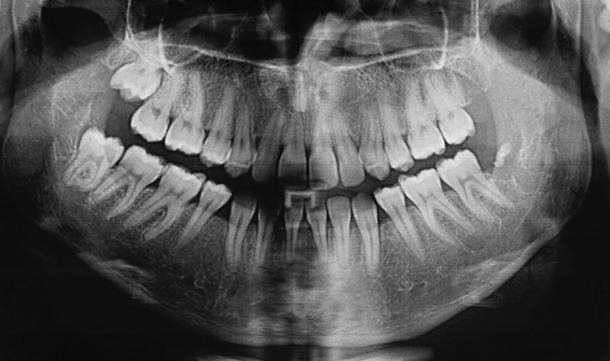

This case report presents a 22-year-old girl with class III malocclusion due to maxillary deficiency. The patient was referred for presurgical orthodontics; however, she rejected the surgery. This case was treated by means of Tongue appliance and slow palatal expansion, followed by lower fixed appliance, reverse chin cup, and upper fixed appliance. Tongue appliance and slow palatal expansion were used at the beginning of the treatment. After 6 months, reverse chin cup and lower fixed appliance were added. Six months later reverse chin cup was removed and upper fixed appliance was mounted. Positive overbite and over jet were achieved after 24 months of active treatment. Nasolabial angle also showed improvement. Nonsurgical treatment of adult class III patients is a difficult procedure; however, this patient was treated nonsurgically.

本病例报告介绍了一名22岁因上颌骨发育不足导致III类错牙合畸形的女孩。该患者被转诊接受术前正畸治疗;然而,她拒绝了手术。本病例采用舌弓矫治器和慢速腭扩展进行治疗,随后使用下颌固定矫治器、反向颏兜和上颌固定矫治器。治疗开始时使用舌弓矫治器和慢速腭扩展。6个月后,增加了反向颏兜和下颌固定矫治器。6个月后,移除反向颏兜并安装上颌固定矫治器。经过24个月的积极治疗,实现了覆牙合和覆盖正常。鼻唇角也有所改善。成年III类患者的非手术治疗是一个困难的过程;然而,该患者接受了非手术治疗。